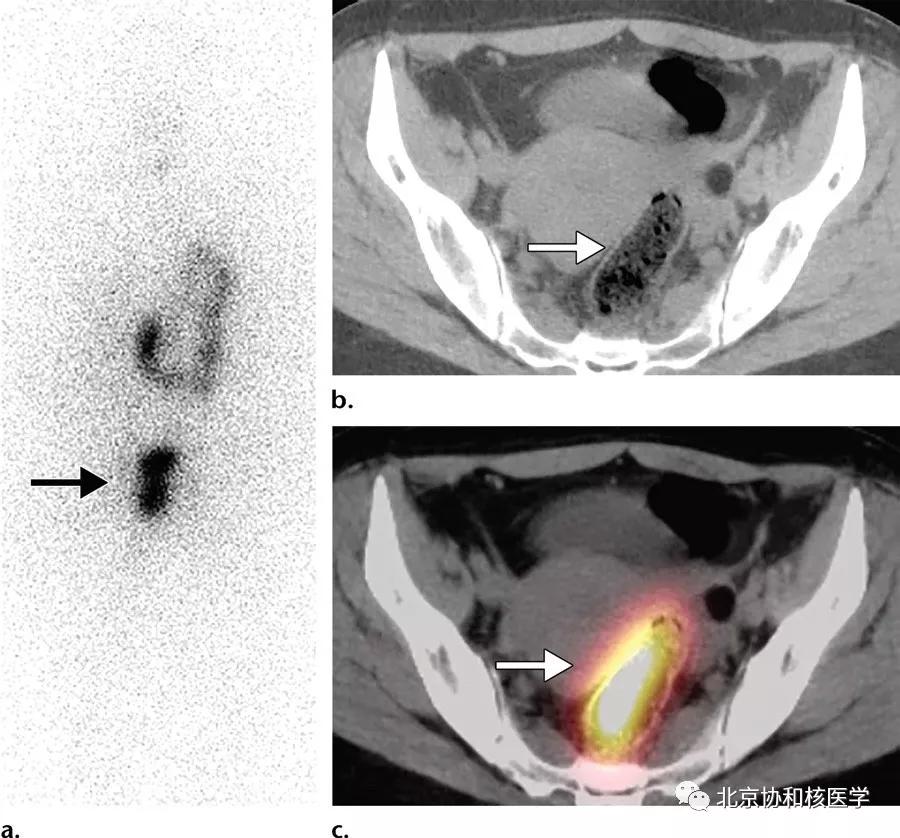

36岁女性,乳头状甲状腺癌甲状腺全切除术后,碘131治疗后7天显像见子宫内膜区摄取,考虑为碘在经血中停留所致:

39岁女性,恶性卵巢甲状腺肿病史,行右侧卵巢切除术、甲状腺切除术、碘131治疗,碘扫可见残余甲状腺摄取、盆腔转移灶摄取及肝转移灶摄取: